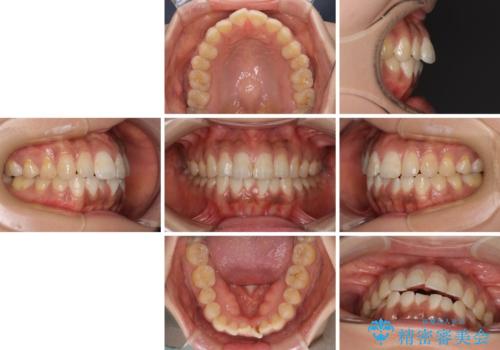

- 前歯のデコボコと上下前歯の隙間を気にして来院された患者様です。

下顎前歯はデコボコのため、歯肉が腫れやすくなっていました。

また、舌突出癖のため、上下前歯の間に隙間ができてしまい、上顎前歯が前方に傾斜している状態でした。